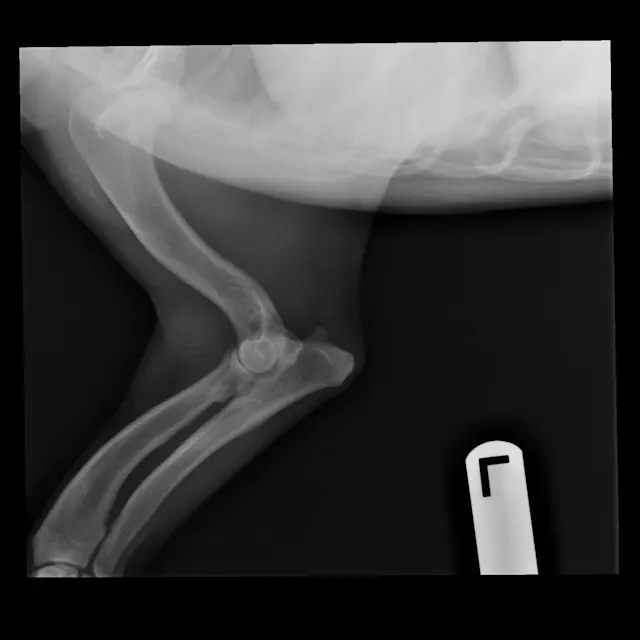

FIGURE 1

Radiographs of Ernest at 8 years of age at a recheck examination

On physical examination, Ernest had bilateral carpal valgus, with pain on manipulation of the carpus and mild hypertrophy of the shoulder musculature. On gait evaluation, slight scuffing of the left front paw was noted. Ernest also had bilateral pain/resistance on extension of the coxofemoral joints and mild atrophy of the quadriceps/hamstrings bilaterally; he also appeared to be “bunny hopping” in the hindlimbs when jogging or climbing stairs. Ernest’s BCS was 4/9, and the remainder of the examination, including a neurologic examination, was within normal limits. Ernest was diagnosed with OA and pain secondary to hip dysplasia and angular limb deformity.